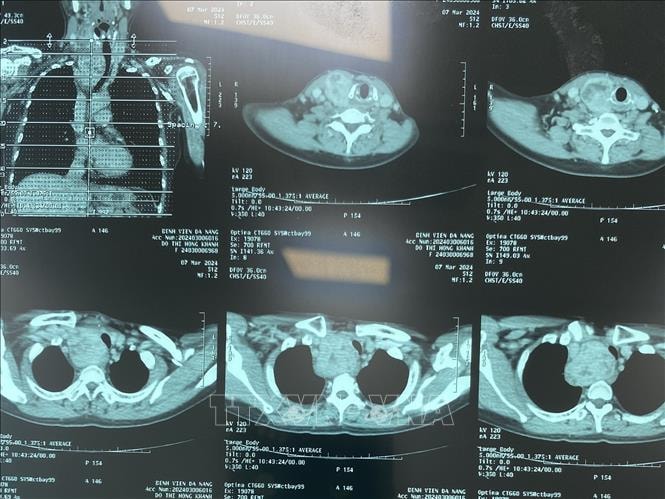

Chẩn đoán hình ảnh không cần phim in vào Quỹ BHYT chi trả- Ảnh 1.

Chẩn đoán hình ảnh X quang.